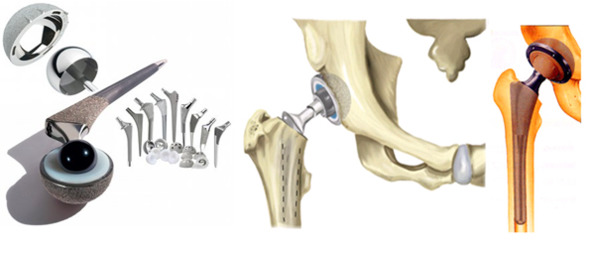

Суставной имплантат

Суставной имплантат

Имплантация суставов и их частей (артропластика). В настоящее время искусственным суставом можно заменить плечевой, локтевой, коленный или бедренный суставы. Возможна имплантация искусственной кисти и суставов пальцев кисти. Реже имплантируют искусственные суставы плюсны или плюснепредплюсневые суставы и суставы пальцев стопы.